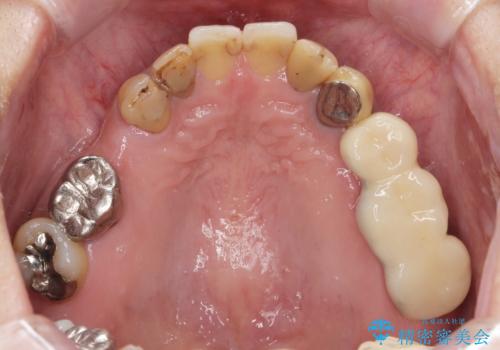

- 「歯の見た目が悪く、奥歯も噛みづらい、しっかりと全体的に治療したい。」と全顎的な治療を希望され来院されました。

虫歯・感染根管・予後不良歯・欠損・不正咬合、複合的な問題を一つづつ丁寧に解決し、将来に渡り不安のない口腔内環境にすべく全体的な総合治療を行っていきます。